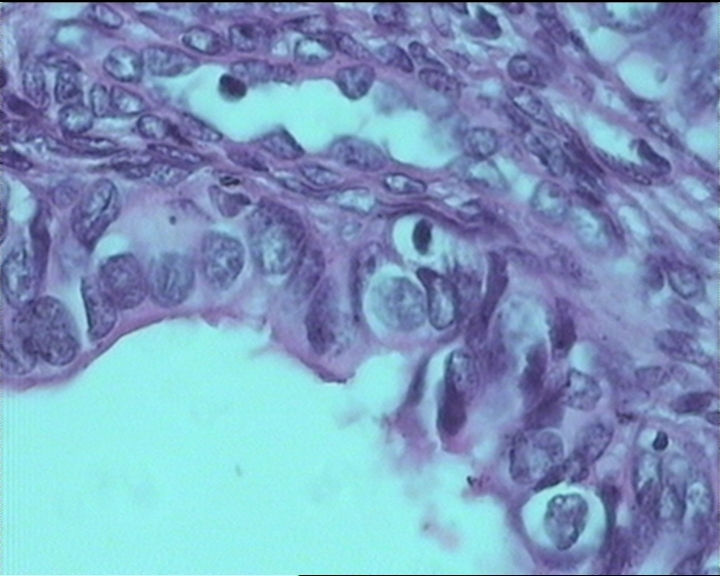

54岁女性,临床“宫颈息肉”送检;巨检:组织一块1。5*1CM,灰红。

输卵管粘膜化生

It is benign. Benign endocervical polyp with tubal metaplasia.

细胞及腺体均有异形,图6、11、16象有纤维间质反应,考虑高级别上皮内瘤变/原位癌,腺癌不能除外。

Sternberg病理学上诊断宫颈原位腺癌的标准是腺体的上皮去粘液分化,呈乳头状或筛网状增生,核分裂易见,这例显然达不到此标准。此例还是归入到腺上皮不典型增生为好。

杨老师说它是良性的,是个颈管内膜息肉伴输卵管上皮化生,良性